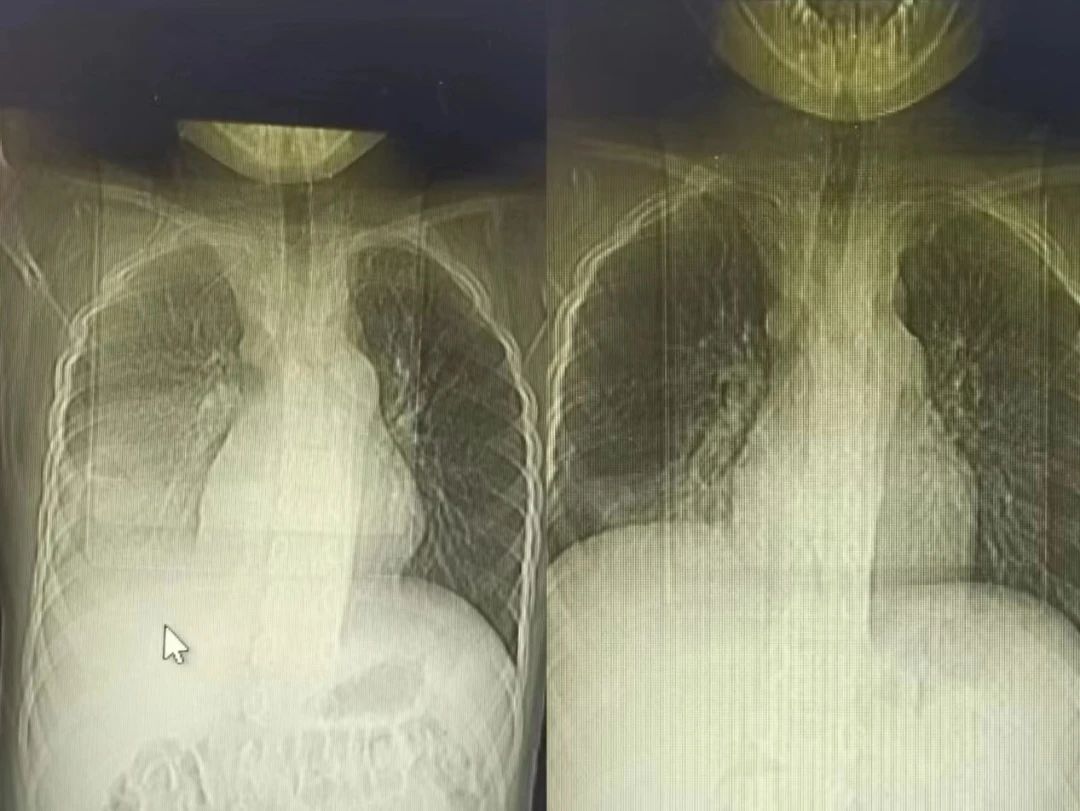

半个多月前,一名9岁的小男孩七七在父母的陪伴下,来到了锦州市妇婴医院(妇幼保健院)小儿呼吸科。因为反复高热、咳嗽10天,辗转于外院治疗6天,病情却逐渐加重,反复39-40度不退,复查的肺CT提示重症肺炎。

接诊后,当班的齐思梦医生敏锐地捕捉到重要信息:每天有将近40度的高热,持续10天;经过正规抗炎治疗6天,完全无效;合并有胸腔积液。

节假日期间,七七出现了间歇性胸痛,疼出了眼泪,又出现了一次低热,家属的心再一次提到了嗓子眼儿。刘铁英主任连忙赶到医院看望他,担心重症肺炎可能出现恢复期的肺栓塞,又紧急联系放射线,放射线曹主任马上安排会诊给他急查了肺增强CT。结果出来后没有发生栓塞,医护人员和家属都松了一口气,考虑跟胸水吸收后引起的胸膜牵扯痛有关系,对症处置后2-3天胸痛消失,发热也很快消失。